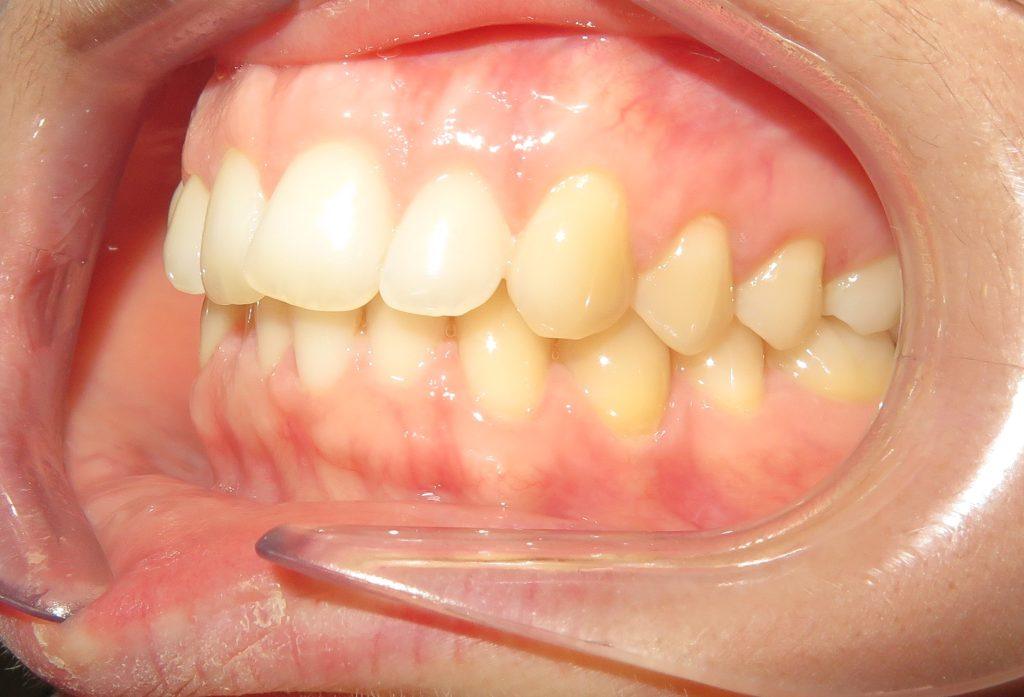

Pacjentka zgłosiła się do nas z takimi problemami, jak:

❌ zwężone łuki zębowe,

❌ tyłozgryz,

❌ głęboki zgryz,

❌ stłoczenia,

❌ zrotowane i starte zęby

Pod opieką Agnieszki Łukowicz, Master of Science Orthodontics została poddana zaawansowanemu leczeniu aparatem stałym ligaturowym, Dzięki czemu udało się osiągnąć znaczące zmiany:

✅poszerzenie luków zębowych,

✅korekta tyłozgryzu,

✅rozwiązanie stłoczenia,

✅odrotowanie zrotowanych zębów,

✅odbudowa startych zębów.

Efekt estetyczny został dopełniony przez wybielanie zębów i odbudowę kompozytową wykonaną przez dr Monikę Niewitecką.

Przedstawiamy piękny i zdrowy uśmiech naszej Pacjentki!